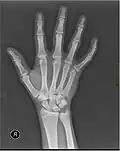

X-ray

X-ray image of right hand with thumb on left. -

In human anatomy, the metacarpal bones or metacarpus, also known as the "palm bones", are the appendicular bones that form the intermediate part of the hand between the phalanges (fingers) and the carpal bones (wrist bones), which articulate with the forearm. The metacarpal bones are homologous to the metatarsal bones in the foot.

Each metacarpal bone consists of a body or shaft, and two extremities; the head at the distal or digital end (near the fingers), and the base at the proximal or carpal end (close to the wrist).